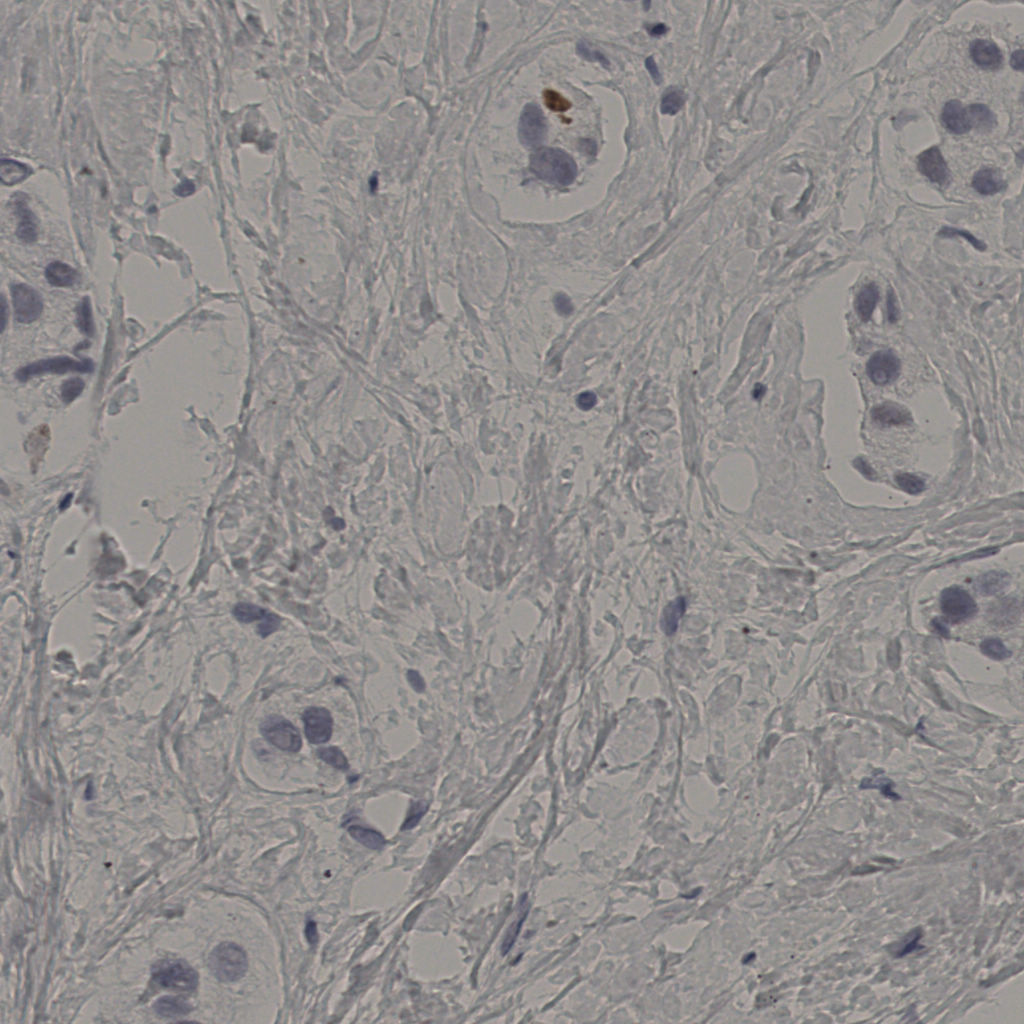

5.31%

Ki67 指数

阴 19502

阳 1093

切片统计

总切片

2970

有效

554

已标记

554

有效率

19%